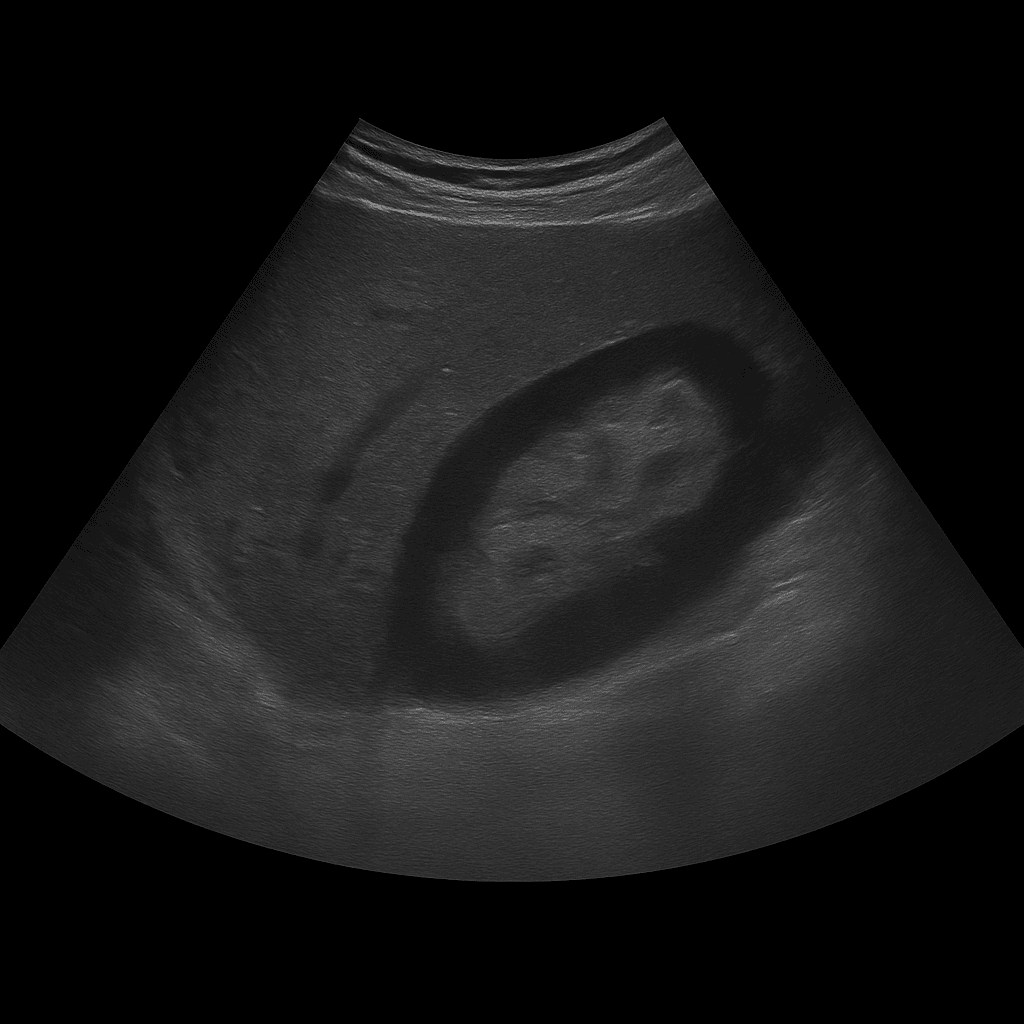

Ett ultraljud av njurarna används för att undersöka njurarnas storlek, form, vävnadsstruktur och blodflöde. Undersökningen utförs av specialistläkare inom radiologi och ger detaljerade bilder i realtid som kan påvisa förändringar som påverkar njurfunktion eller urinflöde. Den används för att utreda bland annat njursten, cystor, vätskeansamling, infektioner eller misstänkta tumörer.

Till skillnad från MR och DT, som ofta används vid mer avancerad kartläggning eller misstanke om tumörer, är ultraljud förstahandsmetoden vid funktionella och strukturella bedömningar. Den kan utföras utan kontrastmedel och visar njurarna i realtid – idealiskt för att upptäcka stenar, cystor eller vätskeansamlingar utan risk för strålning.

Undersökningen utförs medan du ligger på rygg eller sida. En gel appliceras på huden och läkaren för ultraljudsproben över området där njurarna ligger. Båda njurarna bedöms i längd- och tvärsnitt, och vid behov granskas även urinblåsan för att bedöma eventuell påverkan på urinflödet. Undersökningen är smärtfri och tar vanligen 15–20 minuter. Du behöver normalt inte fasta eller förbereda dig, men ibland kan läkaren be dig att dricka vatten före undersökningen för att blåsan ska vara lätt fylld.